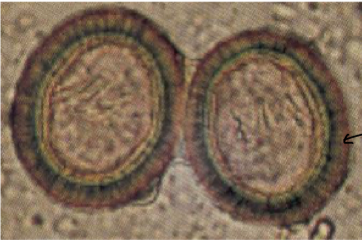

8

Q

identify this parasite

A

echinococcus granulosus egg